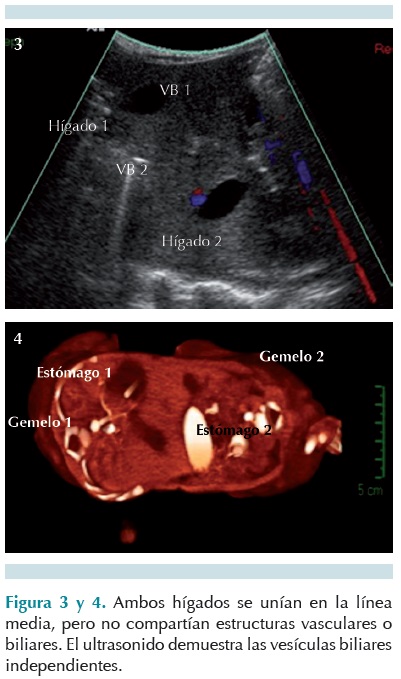

Se realizó un tamiz metabólico ampliado, ácidos orgánicos en orina. Un ultrasonido toracoabdominal (Figuras 3 y 4) mostró un ángulo de separación de la parrilla costal compartida en la cara anterior. Se observó un hígado unido por un istmo central, sin evidencia de que compartieran estructuras vasculares. Se realizó un estudio de tránsito intestinal (Figura 5).